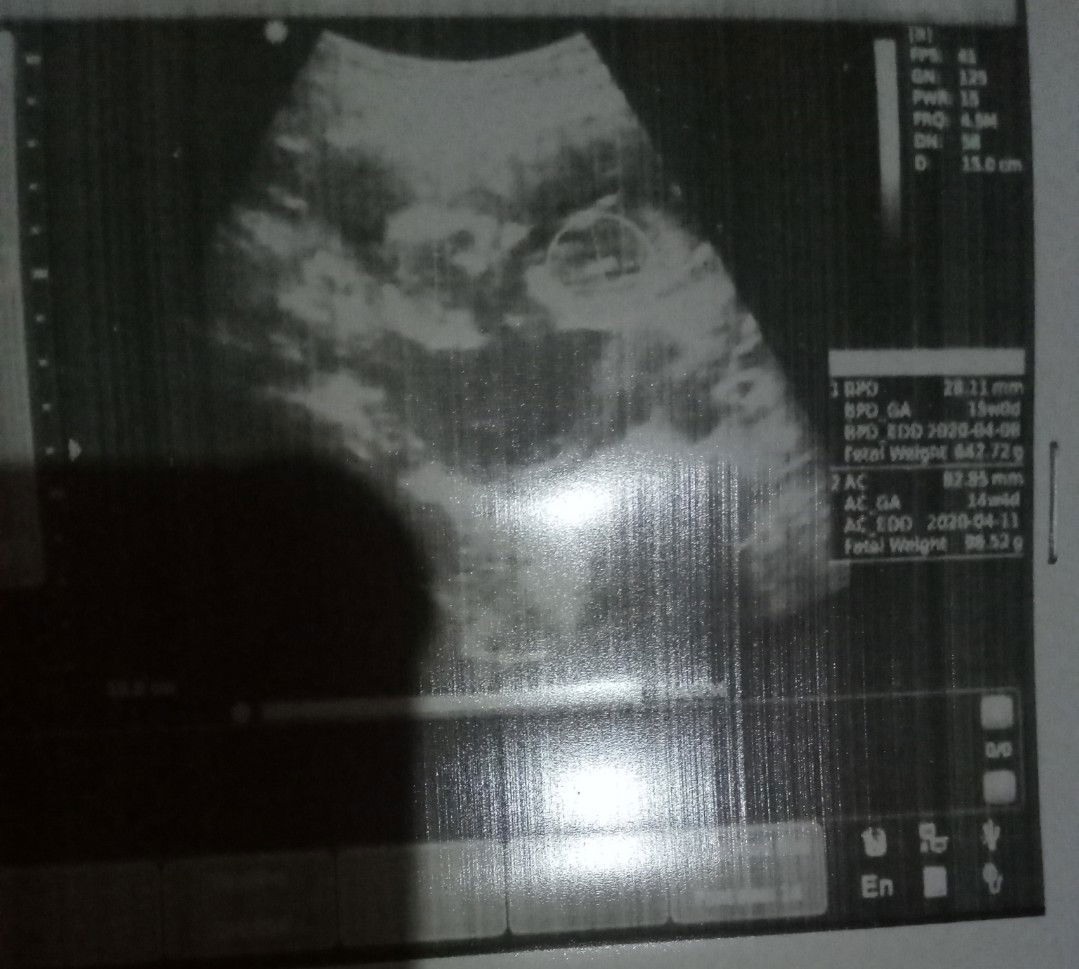

Bun mau tanya yang mana ya berat bayi nya soalnya lupa nanya sama dokter yang tau tolong komen ya di foto usg nya trus kasih lingkaran trims bunda